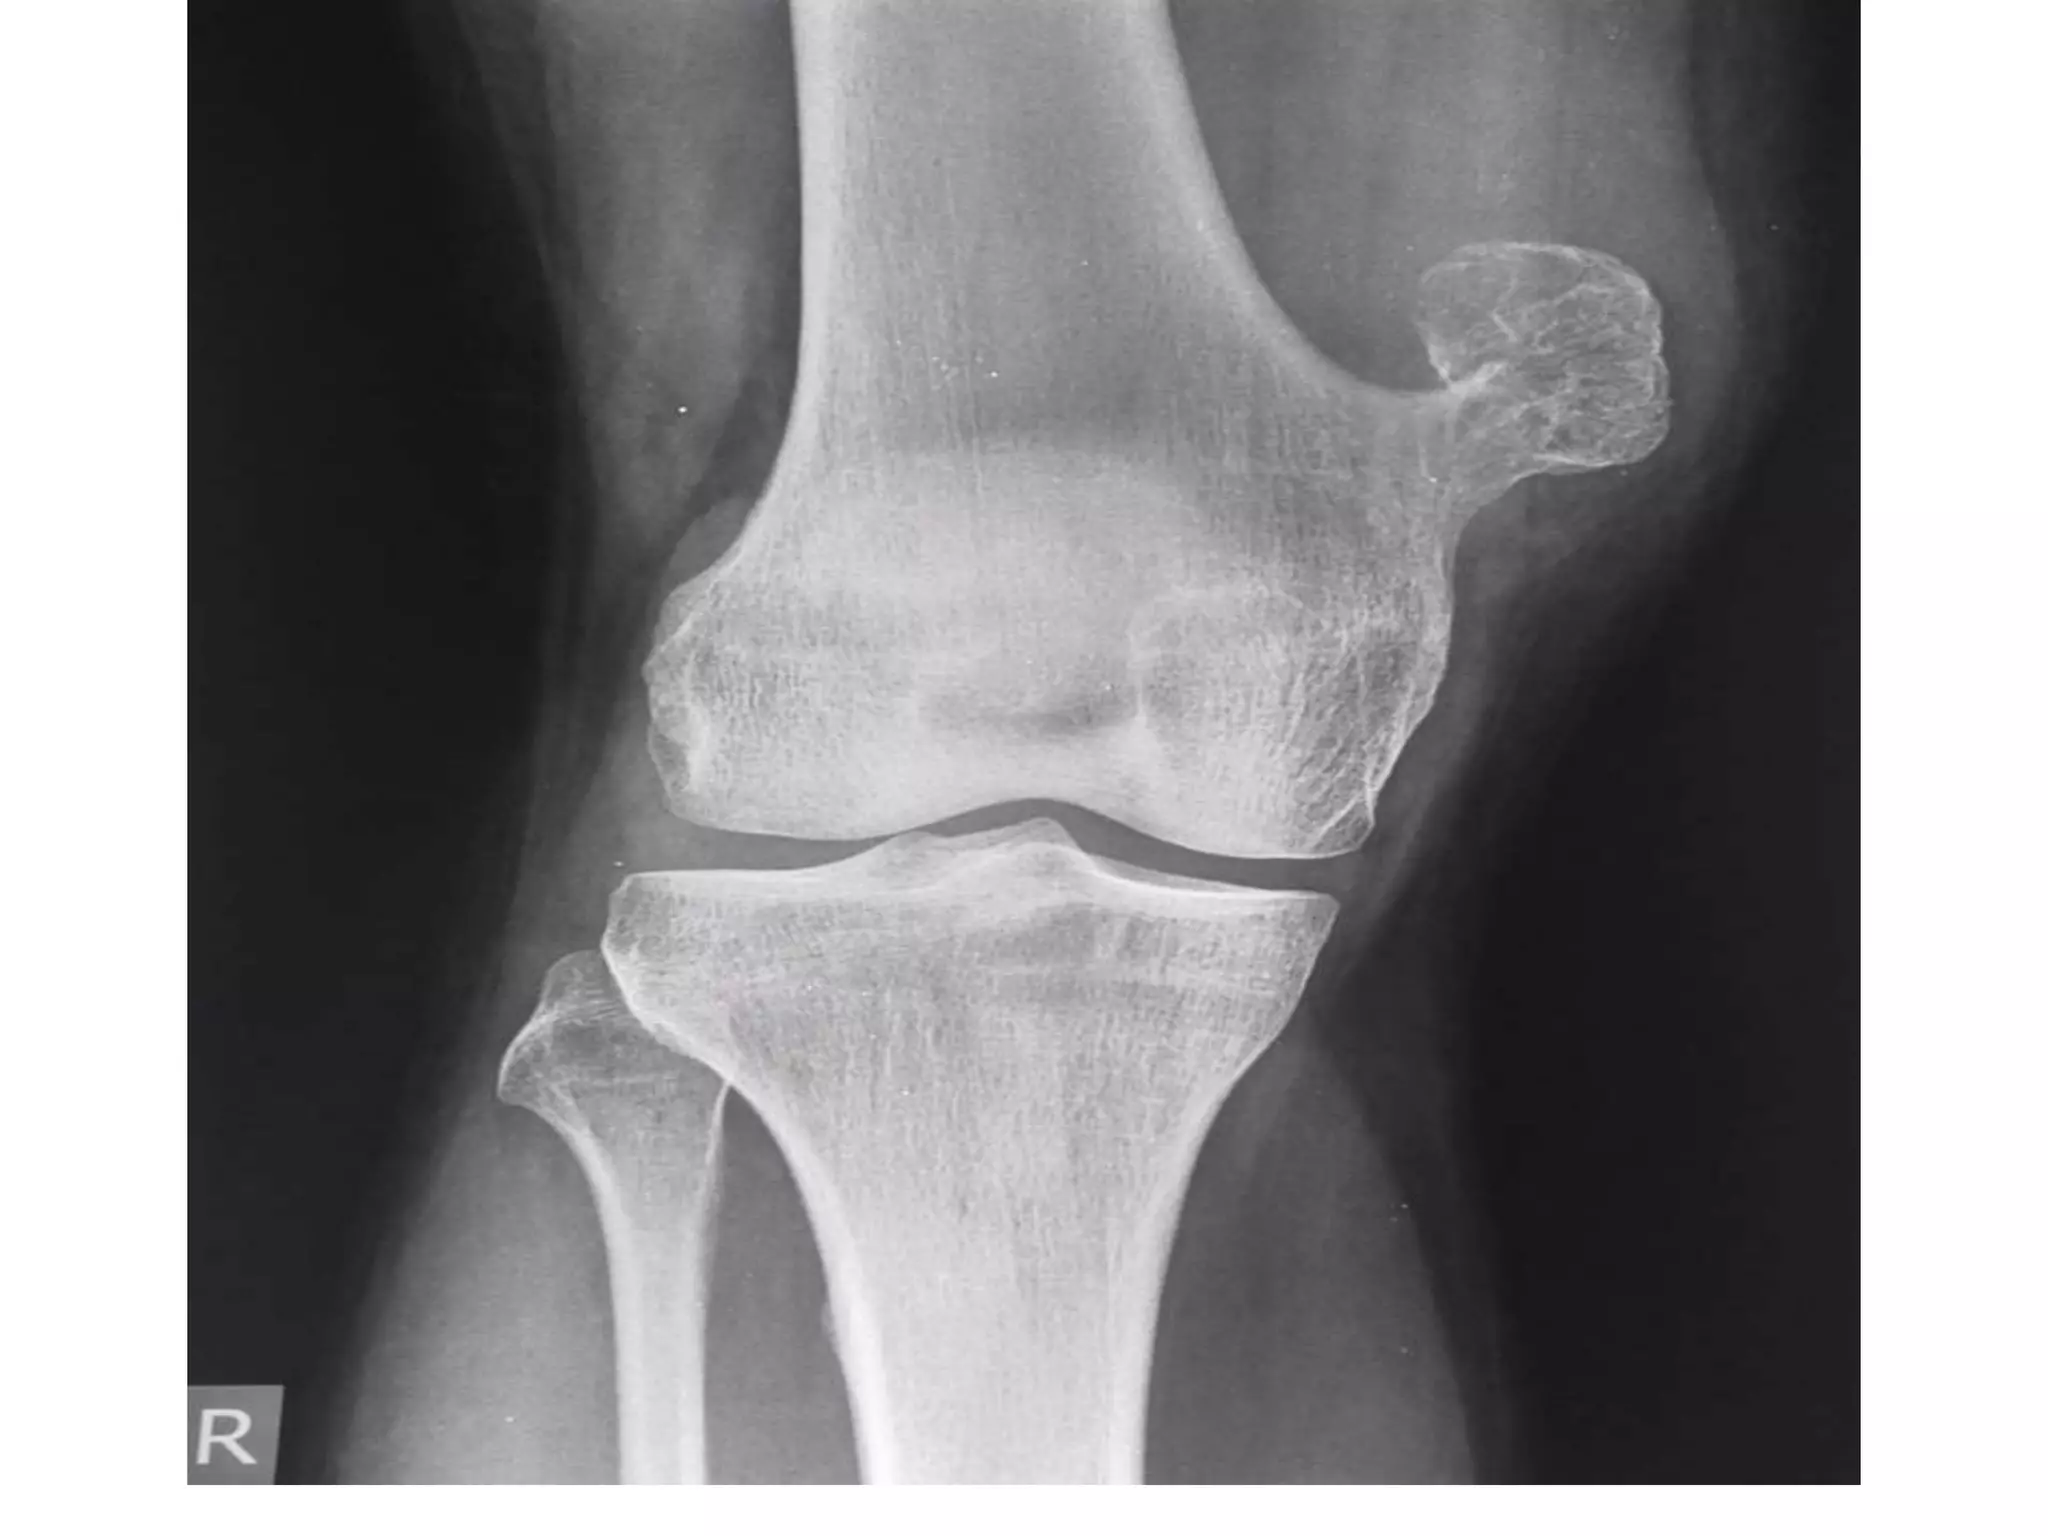

• Giant cell tumor / osteoclastoma at upper end of

left tibia

INVESTIGATIONS

• X-ray of the affected bone

A solitary radiolucent lytic lesion

Eccentrically located at the epiphyseal end of long bone

Bounded by subchondral bone plate

Centre showing soap-bubble appearance due to ridging of

the surrounding bone (homogenously lytic with trabecular

of the remnants of bone traversing it, hence giving a

loculated appearance)

Expansion or ballooning of overlying cortex

Thinning out of the overlying cortex, probably perforated at

places

No calcification within tumor, no reactive sclerosis around

the tumor and no invasion of the adjacent joint